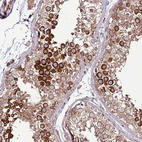

Immunohistochemical staining of human testis shows strong cytoplasmic positivity in cells in seminiferous ducts.